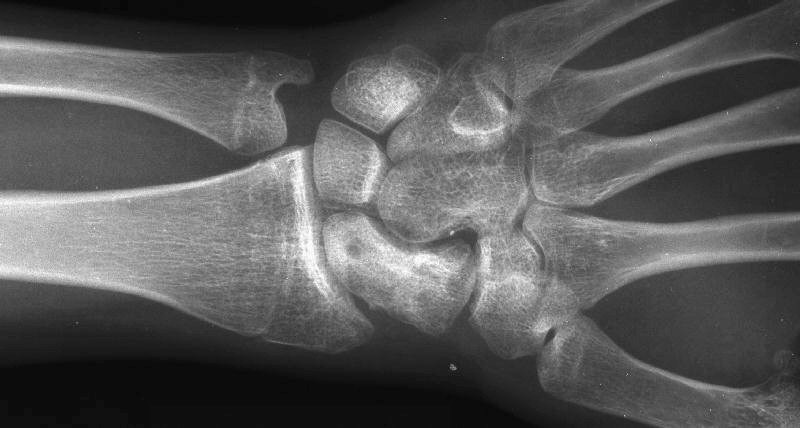

Healed.

The patient requested hardware removal prior to enlisting for military duty. Final films.